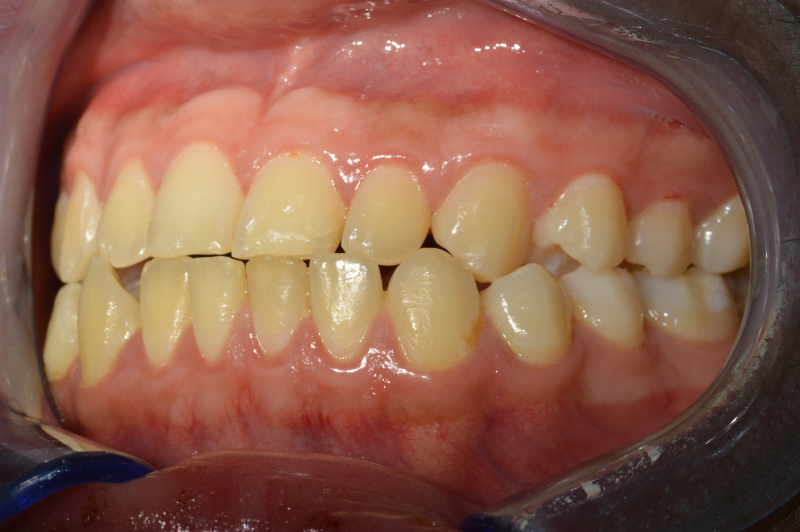

Dopo

Nel 2023 il paziente è stato sottoposto a un intervento chirurgico di avanzamento del mascellare superiore. Lo spostamento delle strutture ossee è stato pianificato virtualmente in fase preoperatoria, utilizzando intraoperativamente un dispositivo di guida (spint/bite) realizzato su misura.

Il trattamento combinato ortodontico-chirurgico ha permesso di correggere in modo efficace la terza classe dento-scheletrica del paziente, con un risultato stabile e armonico sia dal punto di vista funzionale che estetico. L’intervento di avanzamento mascellare, pianificato virtualmente e realizzato senza cicatrici visibili né complicanze sensoriali, ha restituito al paziente un’adeguata occlusione, una maggiore simmetria del profilo facciale e un importante miglioramento della qualità di vita.

Oltre al successo clinico, l’aspetto psicologico ha avuto un ruolo centrale: il paziente ha ritrovato fiducia in sé stesso, superando il disagio sociale legato all’aspetto del viso prima del trattamento.